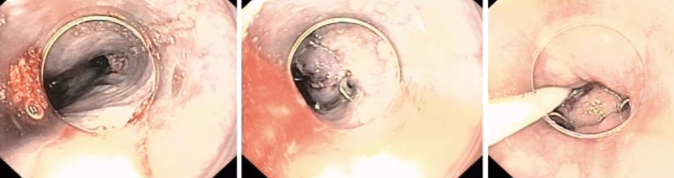

Καλόηθης πολύποδας — κορυφαίο σημείο εντύλιξης (Ευγενική παραχώρηση Dr. V. Penopoulos)